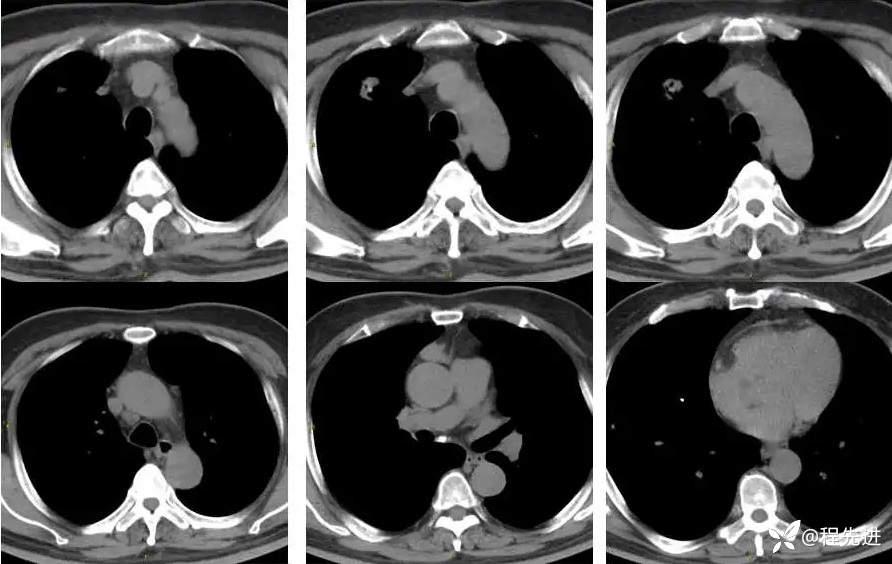

CT平扫:

上排与上面同时间,下排是3月后复查